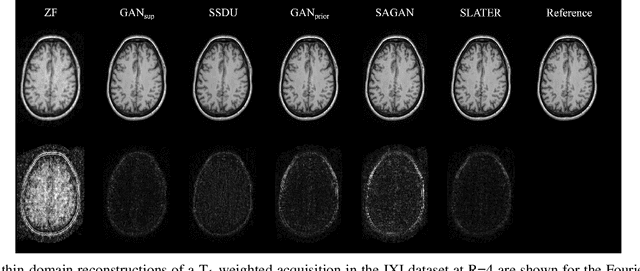

Abstract:Magnetic Resonance Imaging (MRI) produces excellent soft tissue contrast, albeit it is an inherently slow imaging modality. Promising deep learning methods have recently been proposed to reconstruct accelerated MRI scans. However, existing methods still suffer from various limitations regarding image fidelity, contextual sensitivity, and reliance on fully-sampled acquisitions for model training. To comprehensively address these limitations, we propose a novel self-supervised deep reconstruction model, named Self-Supervised Diffusion Reconstruction (SSDiffRecon). SSDiffRecon expresses a conditional diffusion process as an unrolled architecture that interleaves cross-attention transformers for reverse diffusion steps with data-consistency blocks for physics-driven processing. Unlike recent diffusion methods for MRI reconstruction, a self-supervision strategy is adopted to train SSDiffRecon using only undersampled k-space data. Comprehensive experiments on public brain MR datasets demonstrates the superiority of SSDiffRecon against state-of-the-art supervised, and self-supervised baselines in terms of reconstruction speed and quality. Implementation will be available at https://github.com/yilmazkorkmaz1/SSDiffRecon.

Abstract:Supervised deep learning has swiftly become a workhorse for accelerated MRI in recent years, offering state-of-the-art performance in image reconstruction from undersampled acquisitions. Training deep supervised models requires large datasets of undersampled and fully-sampled acquisitions typically from a matching set of subjects. Given scarce access to large medical datasets, this limitation has sparked interest in unsupervised methods that reduce reliance on fully-sampled ground-truth data. A common framework is based on the deep image prior, where network-driven regularization is enforced directly during inference on undersampled acquisitions. Yet, canonical convolutional architectures are suboptimal in capturing long-range relationships, and randomly initialized networks may hamper convergence. To address these limitations, here we introduce a novel unsupervised MRI reconstruction method based on zero-Shot Learned Adversarial TransformERs (SLATER). SLATER embodies a deep adversarial network with cross-attention transformer blocks to map noise and latent variables onto MR images. This unconditional network learns a high-quality MRI prior in a self-supervised encoding task. A zero-shot reconstruction is performed on undersampled test data, where inference is performed by optimizing network parameters, latent and noise variables to ensure maximal consistency to multi-coil MRI data. Comprehensive experiments on brain MRI datasets clearly demonstrate the superior performance of SLATER against several state-of-the-art unsupervised methods.